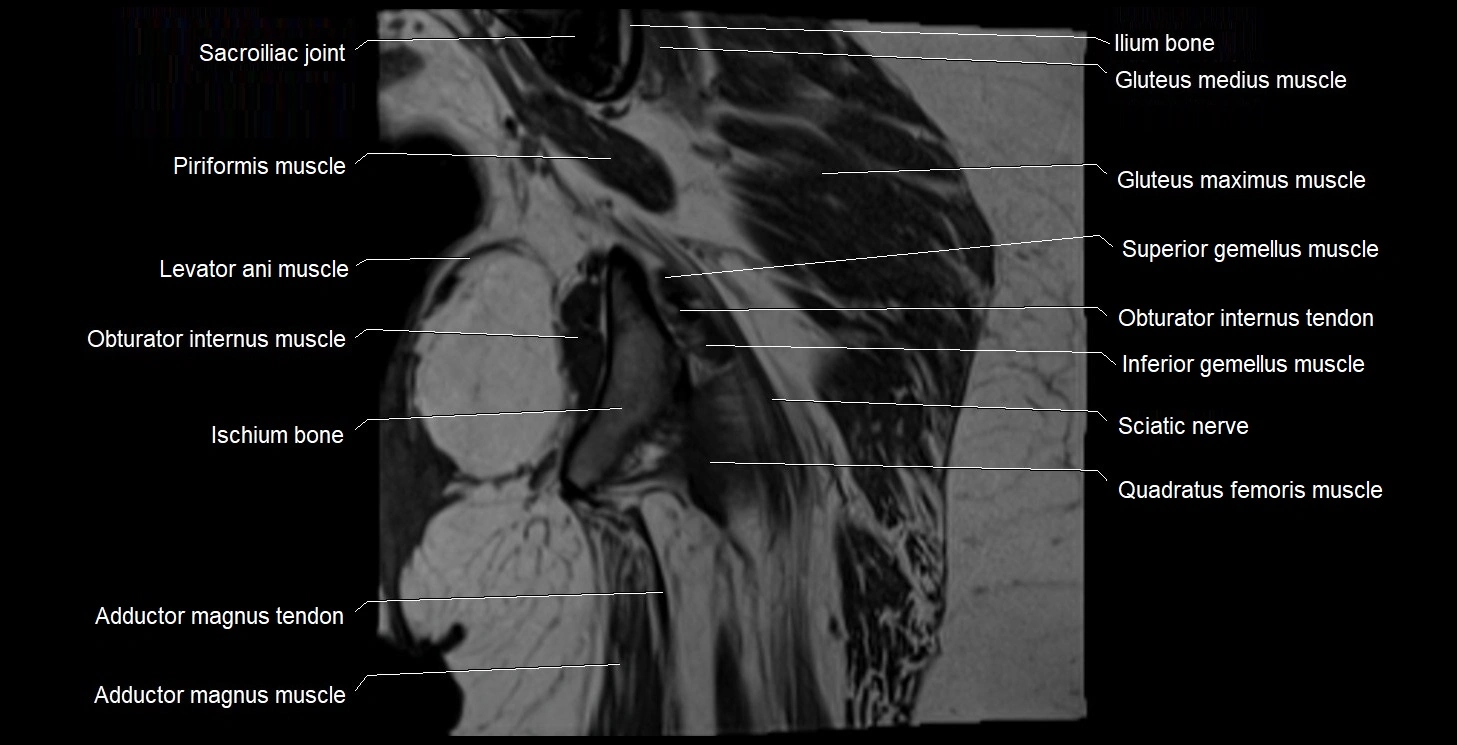

- Sacroiliac joint

- Obturator internus muscle

- Obturator internus tendon

- Levator ani muscle

- Inferior gemellus muscle

- Superior gemellus muscle

- Quadratus femoris muscle

- Ischium bone

- Adductor magnus muscle

- Gluteus maximus muscle

- Gluteus medius muscle

- Ilium bone

- Sacrospinous ligament